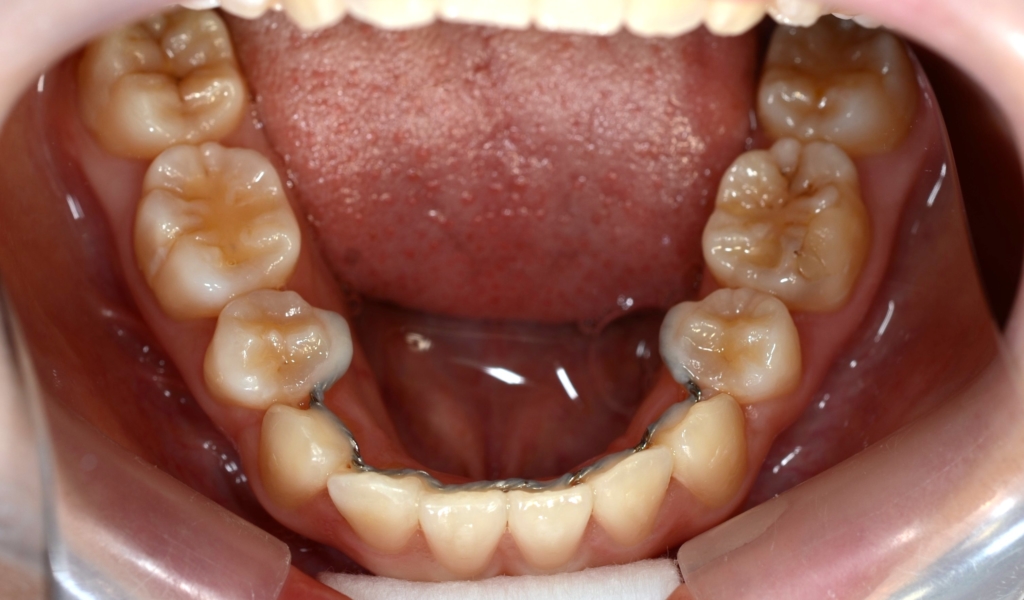

【抜歯】

上下の左右の奥歯を1本ずつ計4本抜歯(4番目の第一小臼歯を抜きました)

【治療装置】

マルチブラケットシステム(ハーフリンガル type)で矯正を開始。

【保定】 上下ともフィックスタイプ&クリアリテーナー